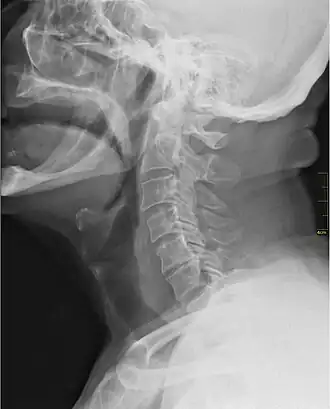

![]() Rayos X mostrando la garganta. | ||

En anatomía, la garganta (de la onomat., garg)[1] o gorja (del francés, gorge 'garganta')[2] es la parte frontal del cuello. Es conocida como faringe la porción del cuello en donde pasa el bolo alimenticio y el aire inspirado. La garganta contiene varios vasos sanguíneos, músculos de la faringe, la tráquea y el esófago. El hioides es el único hueso ubicado en la garganta de los mamíferos.